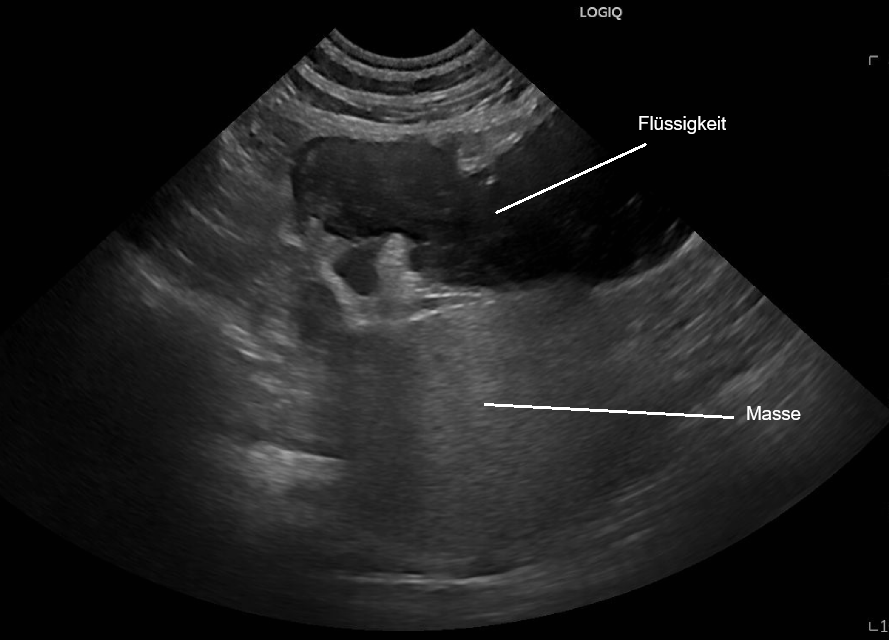

Im Ultraschall wird dann ersichtlich, dass der Hund im Bereich der linken Nebenniere einen Knoten von etwa 5 cm Durchmesser aufweist. Anschliessend an den Knoten befindet sich ein flüssigkeitsgefüllter Raum. Es besteht der dringende Verdacht, dass Maylo an einem Nebennierentumor leidet, welcher zu einer Blutung geführt hat.

Im CT kann der Tumor bestätigt werden, bei der beobachteten Flüssigkeit handelt es sich um Blut. Eine Gewebepunktion diagnostiziert ein sogenanntes Phäochromozytom - ein Tumor der Nebenniere, welcher aus Zellen besteht, welche das Hormon Adrenalin produziert.